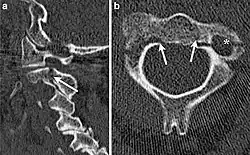

CT scan of hangman's fracture